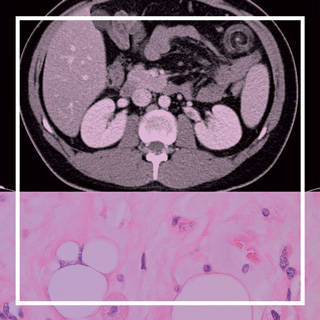

neuroradiology exam image

Residents submit hundreds of cases to the AIRP, but only a handful are designated as the course's best cases.

View a selection of the best cases selected from a recent radiologic-pathology course.